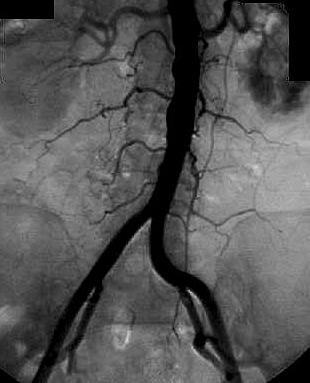

the pathological image-left and the physiological image-right

If you need

a physiological image to compare click here